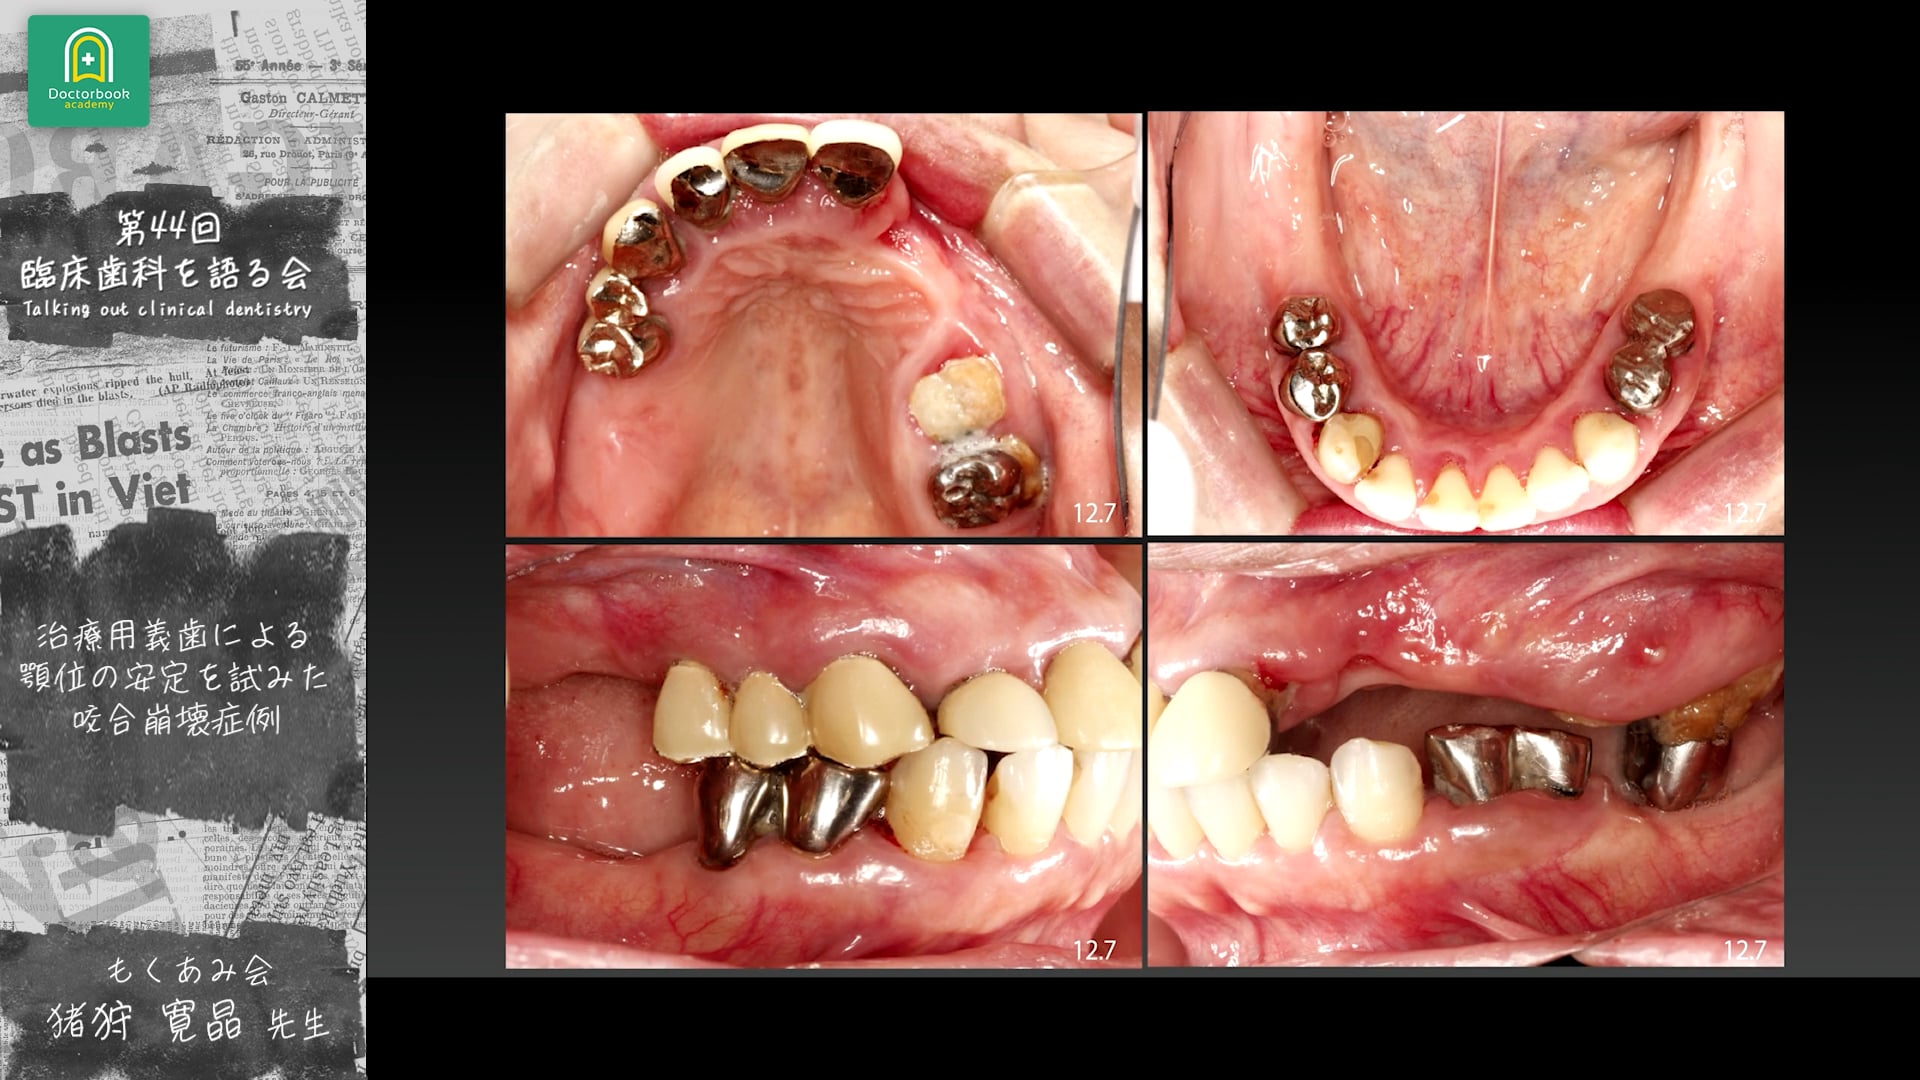

本動画では、猪狩先生が「咬合崩壊症例に対する補綴設計と長期経過」について症例をもとに発表。

震災後に来院した55歳女性患者に対し、残存歯の保存を最大限に考慮した治療計画を実践。

治療用義歯を用いて咬合を確保し、段階的な咬合再構築とプロビジョナル調整を行うことで、上下的偏在を抑制し安定した咬合を獲得。

9年経過後も良好な機能維持を確認し、治療用義歯の活用と患者との情報共有が咬合再建成功の鍵であることを示しました。